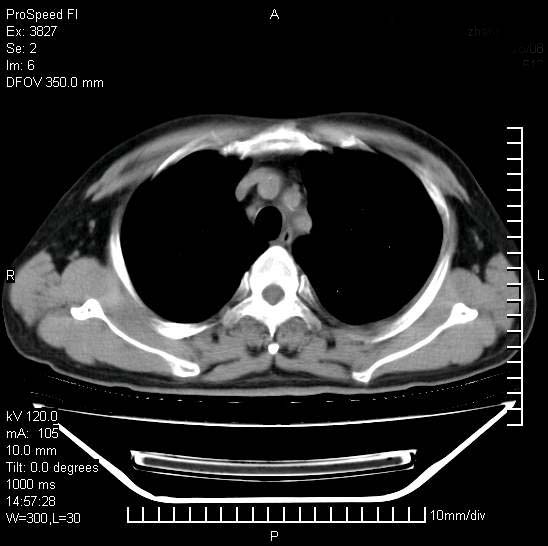

男性,一月前出现右侧肋区疼痛,较剧烈,干咳,无发热,自诉使用抗炎药后缓解,几天前又出现左侧剧烈疼痛,

发热,体温38。9,今天ct,考虑左侧包裹性脓胸,胸腔积液,右上中肺小斑片影,结核/炎症?胸水未见恶性细胞。